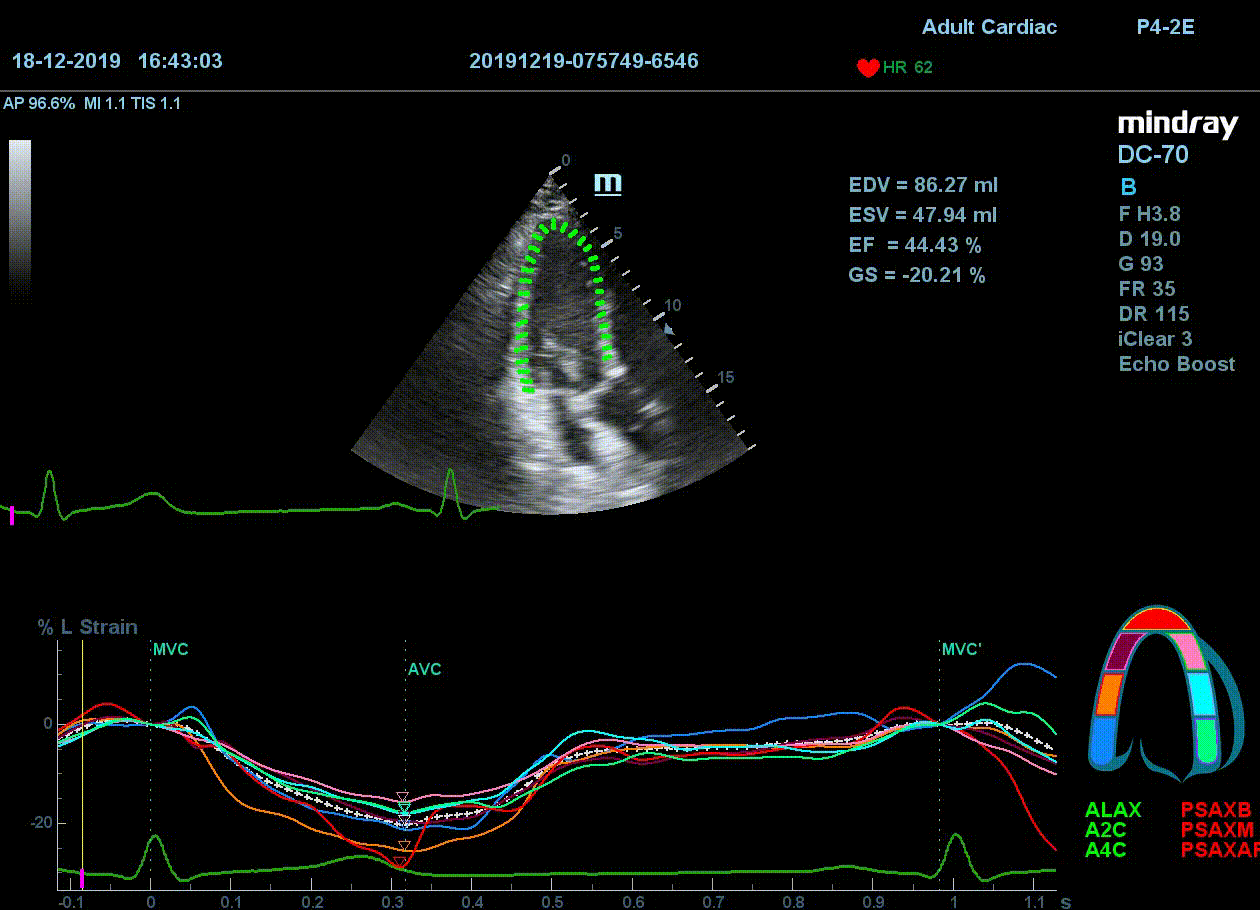

Как работать с данным методом? Для Longitudinal Strain необходимо записать видео петли апикальных сечений в память прибора: 4С, 3С, 2С. Для повышения качества трекинга рекомендуется производить запись на выдохе пациента. Затем произвести разметку по линии эпикарда, перикарда и центра миокарда. Нажатием кнопки «начать слежение» активируется программный алгоритм, видео петля оживает вместе с размеченными точками-speckle’ами. При необходимости производится коррекция. После анализа всех трех сечений можно получить данных продольной деформации как в среднем значении, так и по каждому сегменту миокарда левого желудочка. Нормальным показателем считается Longitudinal Strain -20%. Нижней границей -14%.

Видео примеры на приборе Mindray DC 70